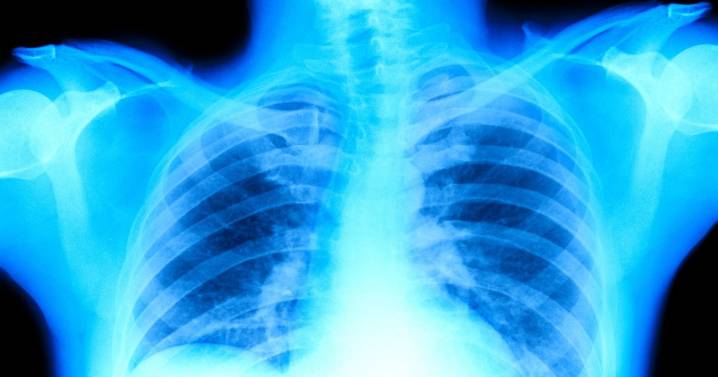

Lung cancer is a killer, claiming the lives of more Americans than any other type of cancer.

That’s because it’s often found late, when it has already spread, says Dr. Humberto Choi, a pulmonologist at the Cleveland Clinic who specializes in thoracic oncology, the diagnosis and treatment of cancer in the chest.

More people die of lung cancer than of colon, breast and prostate cancers combined, according to the American Cancer Society . November is